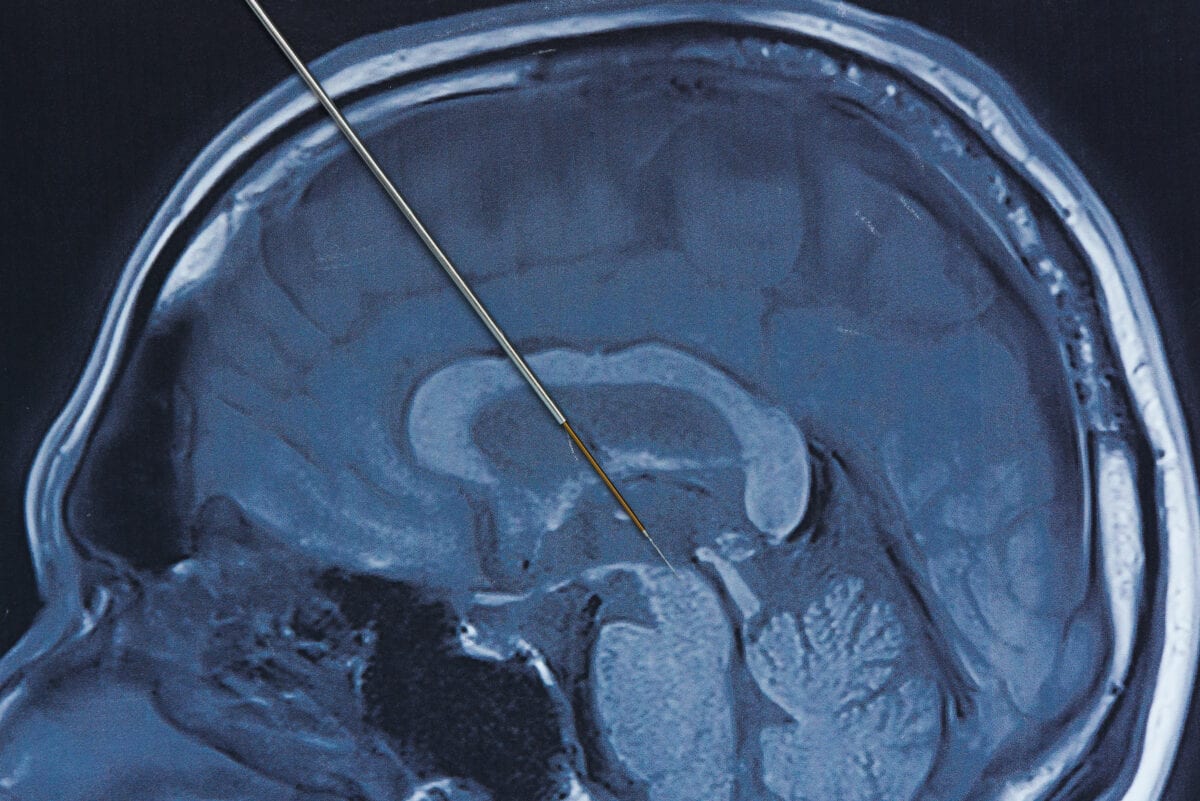

Σημαντική χειρουργική διαδικασία είναι η βαθιά διέγερση εγκεφάλου. Στη βαθιά εγκεφαλική διέγερση (DBS), οι χειρουργοί τοποθετούν ηλεκτρόδια σε ένα συγκεκριμένο τμήμα του εγκεφάλου σας. Τα ηλεκτρόδια συνδέονται με μια γεννήτρια που εμφυτεύεται στο στήθος σας κοντά στην κλείδα σας που στέλνει ηλεκτρικούς παλμούς στον εγκέφαλό σας και μπορεί να μειώσει τα συμπτώματα της νόσου του Parkinson. Ο γιατρός σας μπορεί να προσαρμόσει τις ρυθμίσεις σας όπως είναι απαραίτητο για τη θεραπεία της κατάστασής σας.

Ποιοι οι κίνδυνοι σε περίπτωση χειρουργικής επέμβασης;

Η χειρουργική επέμβαση περιλαμβάνει κινδύνους, συμπεριλαμβανομένων λοιμώξεων, εγκεφαλικού επεισοδίου ή αιμορραγίας στον εγκέφαλο. Μερικοί άνθρωποι αντιμετωπίζουν προβλήματα με το σύστημα DBS ή έχουν επιπλοκές λόγω διέγερσης και ο γιατρός σας μπορεί να χρειαστεί να προσαρμόσει ή να αντικαταστήσει ορισμένα μέρη του συστήματος. Η βαθιά εγκεφαλική διέγερση προσφέρεται πιο συχνά σε άτομα με προχωρημένη νόσο του Parkinson που έχουν ασταθείς αποκρίσεις στη φαρμακευτική αγωγή (λεβοντόπα).